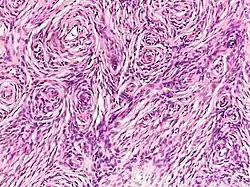

Neurofibroma

A neurofibroma is a benign nerve-sheath tumor in the peripheral nervous system. In 90% of cases, they are found as stand-alone tumors (solitary neurofibroma, solitary nerve sheath tumor[1] or sporadic neurofibroma[1]), while the remainder are found in persons with neurofibromatosis type I (NF1), an autosomal-dominant genetically inherited disease. They can result in a range of symptoms from physical disfiguration and pain to cognitive disability.

Neurofibromas arise from nonmyelinating-type Schwann cells that exhibit biallelic inactivation of the NF1 gene that codes for the protein neurofibromin.[2] This protein is responsible for regulating the RAS-mediated cell growth signaling pathway. In contrast to schwannomas, another type of tumor arising from Schwann cells, neurofibromas incorporate many additional types of cells and structural elements in addition to Schwann cells, making it difficult to identify and understand all the mechanisms through which they originate and develop.[3]